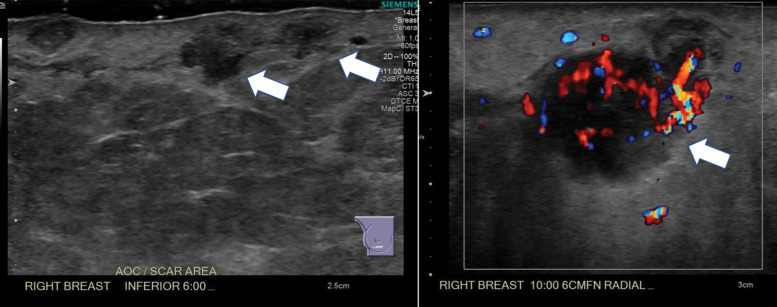

If a clinically indeterminate palpable lump is felt along the scar, imaging workup should be performed. As with chest wall masses, US should be performed first when a palpable mass is identified along the mastectomy scar. A small study by Rissanen et al (63) found that US had 91% sensitivity in evaluation of the mastectomy site. The addition of US has proved to be more accurate than mammography in the setting of a palpable lump, as recurrence tends to be close to the skin surface (40,63) (Fig 15). If enough tissue is present, mammographic views may be helpful in excluding benign causes such as fat necrosis before making decisions regarding biopsy.

Figure 15a.

Recurrence at the mastectomy scar. (a) Color Doppler (left) and gray-scale (right) US images at the areas of palpable concern show a subcutaneous, highly vascular, irregular mass at the central chest wall and an indistinct hyperechoic area inseparable from the skin at the lateral scar (arrowheads in right image). (b) Axial PET/CT images show metabolic activity in the soft-tissue mass (circle) and along the expected location of the mastectomy scar (small arrows), with a focal area of uptake laterally (large arrow). Surgical excision of the palpable mass and scar nodule yielded invasive ductal cancer involving both dermal and adipose tissue, with extensive permeation of dermal and subcutaneous lymphatics by tumor emboli.